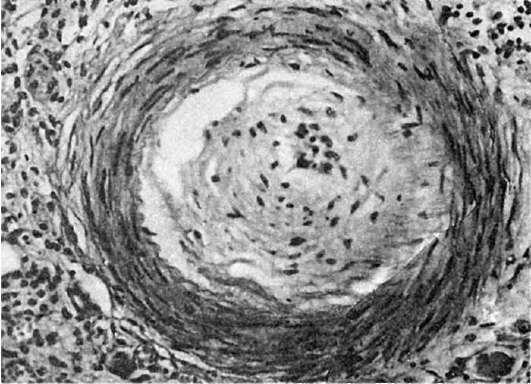

Патологическая анатомия. На основании исследования биоптатов, взятых у лиц, работающих с клепальными молотками, установлено, что на почве спазма в сосудах появляются изменения типа облитерирующего эндартериита (рис. 347). В связи с наличием изменений сосудов появляются трофические изменения в коже и ногтях, развивается гангрена пальцев, ступней. Длительное давление на мышцы инструментов, изменения в спинном мозге и в соответствующих периферических нервах ведут к атрофии мышц предплечья, надлопаточной области, дельтовидной и ромбовидной мышц. В костносуставном аппарате - локтевом и плечевом суставах, костях кисти - обнаруживают повреждение сухожилий, мышц,

Рис.

347. Вибрационная болезнь. Изменения сосуда типа облитерирующего эндартериита